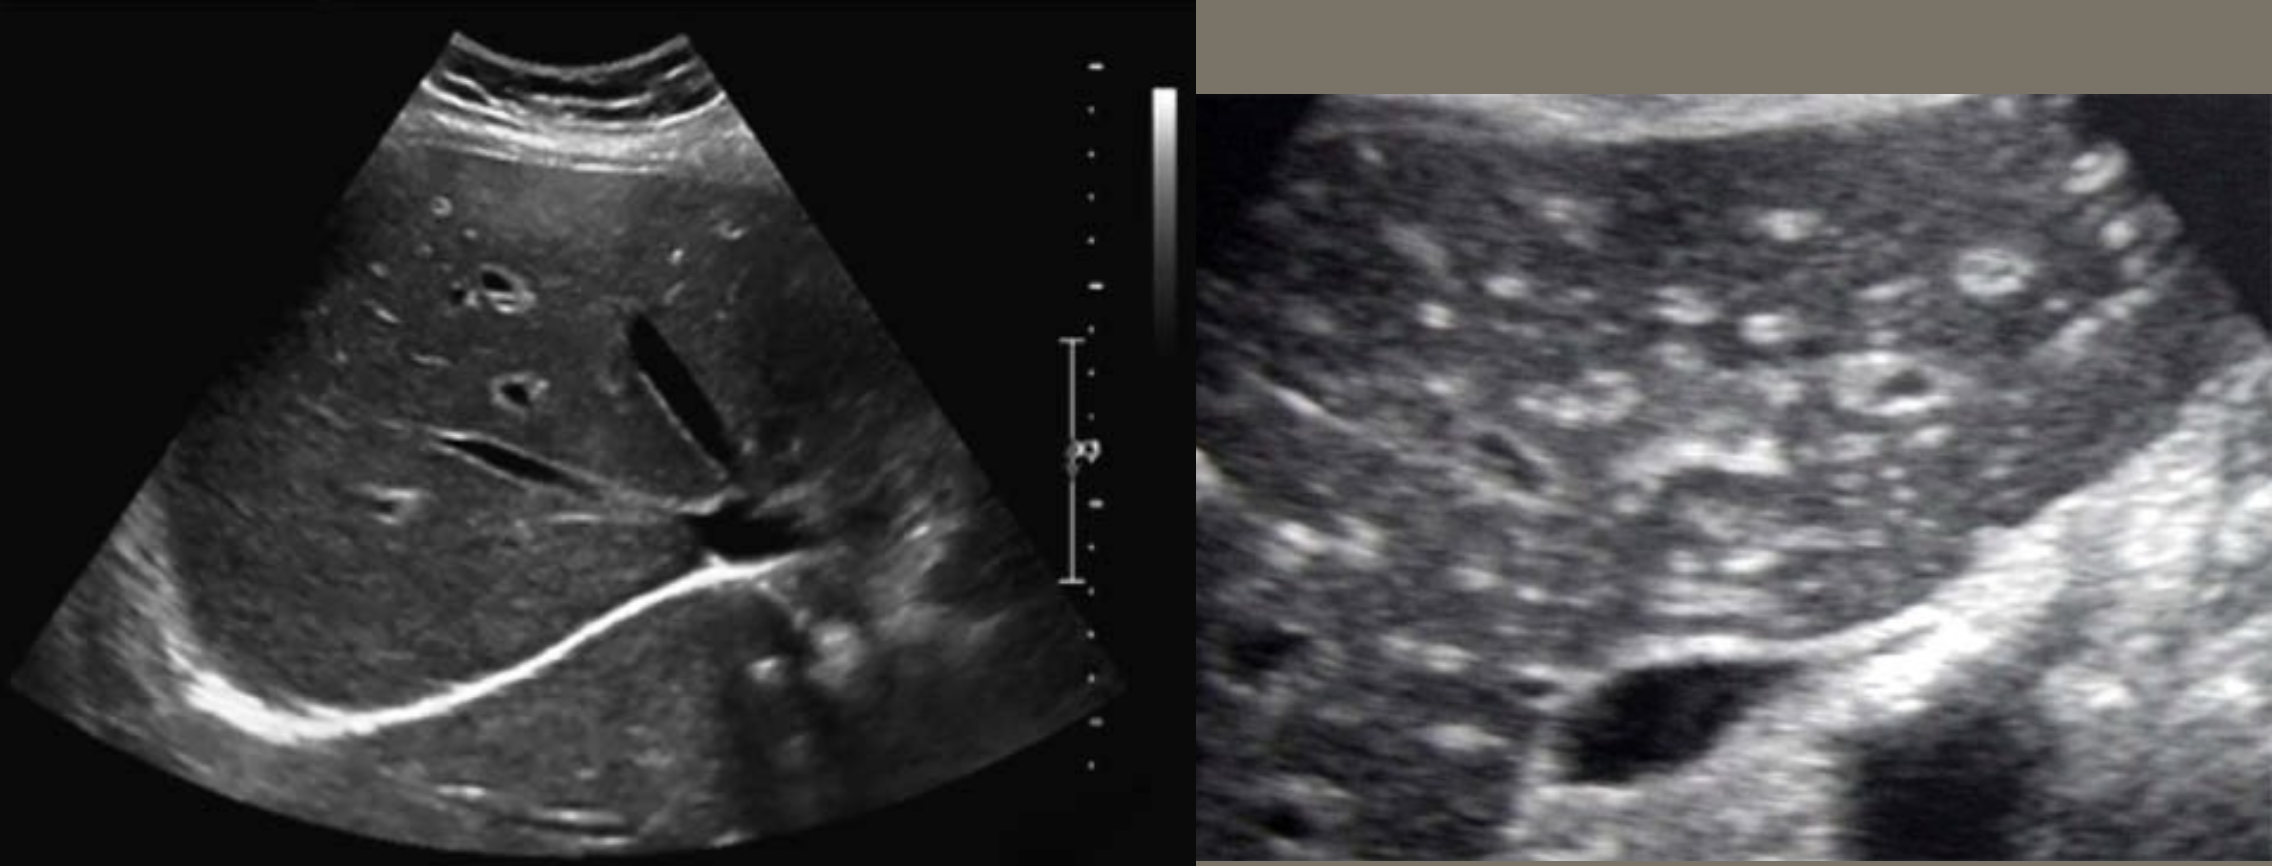

2D US presentation: thin echogenic linear membrane fluttering in lumen creating a true and false lumen

color doppler: fill in both channels → pw shows regular flow in true and weak/no flow in false; asymmetrical kidney perfusion

DDX: AAA (focal dilation, no intimal flap)